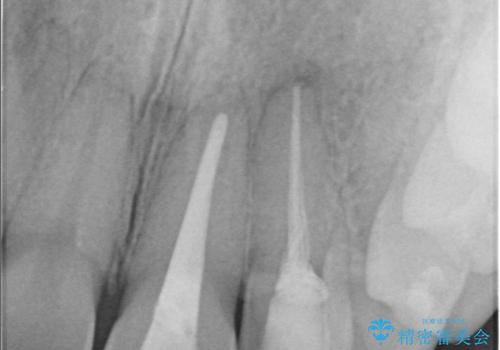

治療内容:

左上2番に対して精密根管治療を実施し、感染源の除去を行いました。その後、左上1、2番ともにオールセラミッククラウンによる補綴を行い、審美的な修復を行いました。

根管治療では、ラバーダム、マイクロスコープ、根管をしっかり洗浄するための専用器具の使用が必須となる治療です。

徹底した洗浄により高い治療効果が得られます。